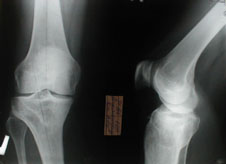

Глубокоуважаемые коллеги. Просьба оказать консультационную помощь Женщина 40 лет. ДТП в 1996: открытый перелом левого бедра, мыщелковый правой голени.

В настоящее время укорочение левой н/конечности 4 см, объем движений левого колена до 70 градусов, патологическая подвижность в области перелома. Планируем дистракцию с помощью аппарата до выравнивания с длиной правой конечности, а вторым этапом резекцию концов отломков бедра и остеосинтез штифтом через интеркондиллярную вырезку.Остеотомию правой б/б кости. Резецированные участки возможно пойдут на заполнение остеотомированной зоны б/берцовой кости. Вопросы по правильности такого планирования, по компоновке аппарата (темп дистракции, жесткость фиксации дистального отломка). Максимов Б.Ю. Сердобск, Пензенская обл.